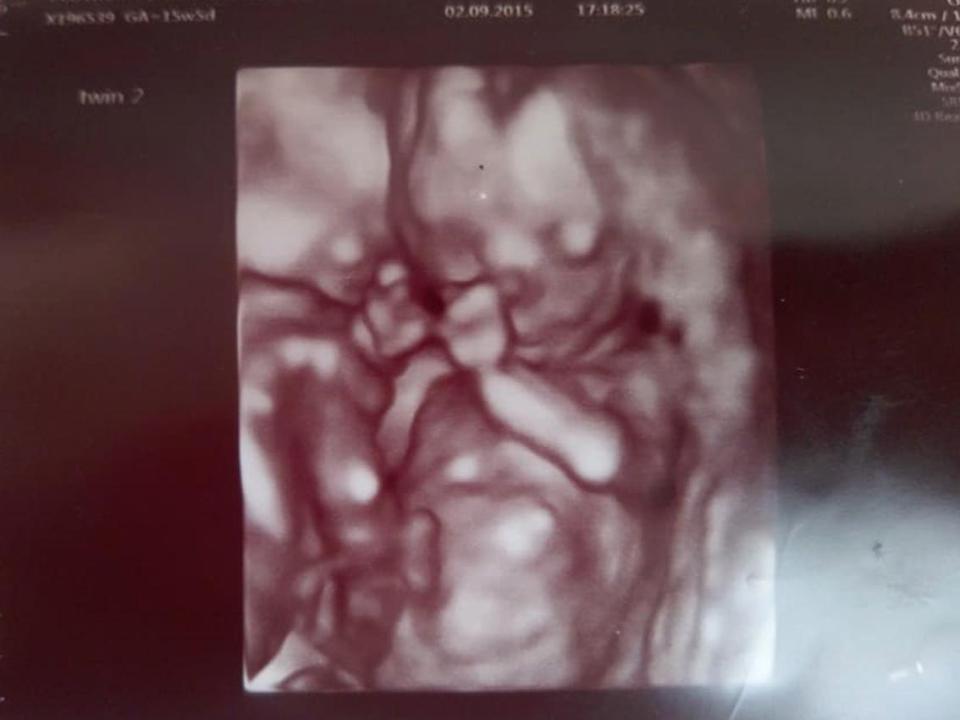

Reuben and Theo, now 22 months, were monoamniotic in the womb, meaning they shared one amniotic sac and risked strangling each other with their umbilical cords.

But incredibly the twins held hands and stayed tightly wrapped around each other throughout the entire pregnancy which stopped them getting tangled in the cords.

But everything changed at the 12-week scan with a specialist sonographer, when Vicky and Chris saw the twins had moved into a lifesaving embrace.

“To our astonishment, at the 12-week scan, we saw that they were cuddling each other and holding hands,” Vicky said.

“They were keeping each other alive by staying still, so their umbilical cords didn’t get tangled.”